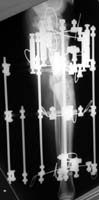

Attached are X-rays of my right leg three months after surgery with Ilizarov fixation.

According to the orthopaedic surgeon, they show solid callus formation on the medial side, while some gaps remain on the lateral side. There is no infection at the wire sites or anywhere else. The frame is to remain attached for one or two months longer. I find it to be much less of a burden than I expected. I am walking with full weight-bearing (no crutches or cane), though not yet with full balance, due to muscle atrophy. My walking is nearly pain-free, except for severe but transient pain in the center of the knee when descending stairs. I believe this is related to the unavoidably high placement of the uppermost wires, and it should cease after the frame is removed. As measured on the X-ray films, the difference in leg length is now five mm, compared with pre-op 3.5 cm. If the tibia continues to solidify and stays in its present configuration after removal of the frame, I will have escaped the judgment of Ecclesiastes 1:15 ('A crooked thing cannot be made straight'). I will inform the List of progress at six months post-op.